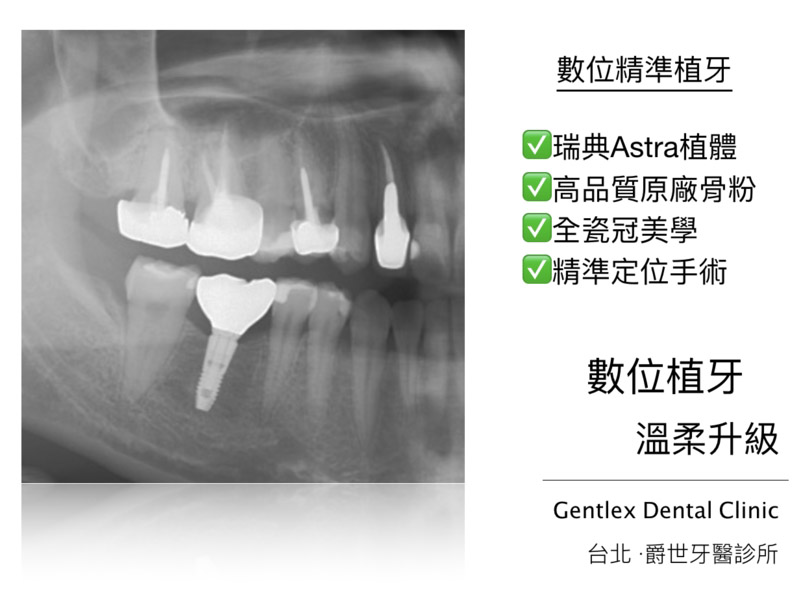

數位植牙 右下第一大臼齒重建